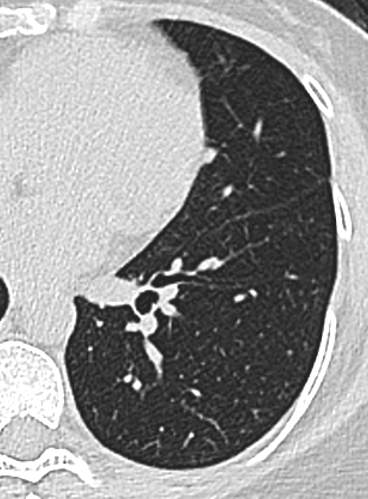

中年女性,既往体健。

21年底左下肺,直径5.2mm: